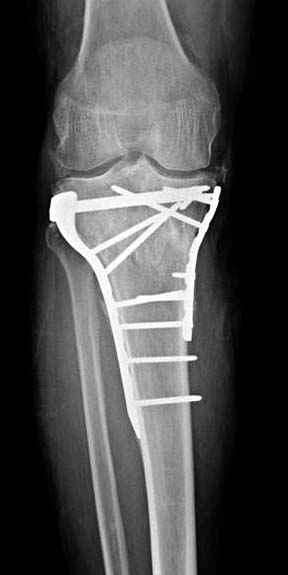

Отдельные переломы тибиал плато и перелом проксимальной трети большеберцовой кости отличаются от переломов тибиал плато с вовлечением диафиза. Здесь перелом тибиал плато типа Schatzker VI, полученный в результате высокоэнергетической травмы. Перелом метафиза образовал отрыв суставной поверхности от диафиза с вовлечением медиального и латерального мыщелков. Двухмыщелковые переломы из-за укрочения опасны развитием компартаментального синдрома, повреждением латерального мениска и связок.

При переломах одного из мыщелков тибиал плато+дополнительный перелом проксимальной трети большеберцовой кости можно применить комбинированный вариант фиксации, т.е. мыщелок винтами или пластиной, а для диафиза можно установить гвоздь. В данном варианте потеряно преимущество гвоздя , из-за серьезной травмы суставной поверхности нельзя нагружать ногу несколько месяцев. А без нагрузки гвоздь просто заполнитель пространства внутри кости!

На вашем место я бы подождал с фиксацией до готовности кожных покровов, и за это время можно было подобрать соответствующий фиксатор, т.е более длинная пластина снаружи и медиальная пластина на апексе перелома как подпорка. Здесь приемлем как раз минимальный доступ.

Здесь пару случаев для сравнения,...в первых 1-4 слайдах метод фиксации одним фиксатором, как видно после 8 месяцев сохранилась ось. С 5 по 9 вариант двумя пластинами...